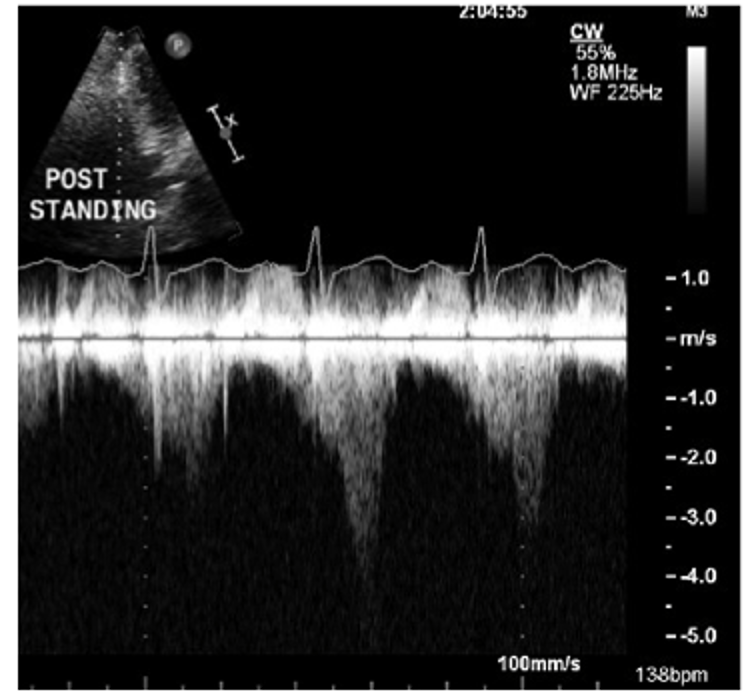

After exercise stress echocardiography, an LVOT gradient of 50 mm Hg, due to SAM and mitral-septal contact, were detected. Mild septal bulge and normal systolic function were appreciated. Source: NYU Langone Health